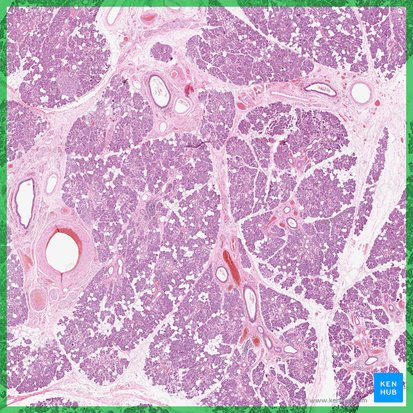

Histologie

Die Gl. submandibularis besitzt sowohl seröse als auch muköse Endstücke, die regional unterschiedlich stark vertreten sind. Insgesamt finden sich jedoch mehr seröse Endstücke. Seröse Regionen enthalten viele Streifenstücke, muköse Bereiche liegen häufig als gemischte Endstücke vor, bei denen seröse Endstücke den mukösen Tubuli aufgelagert sind (von-Ebner-Halbmonde). In den Bindegewebssepten verlaufen Nerven, Blut- und Lymphgefäße sowie Ausführungsgänge mit hochprismatischem Epithel. Die Endstücke sind von Myoepithelzellen umgeben, die eine Kontraktion und damit ein Herausdrücken des Sekrets ermöglichen. Der Ductus submandibularis weist ein mehrreihiges bis mehrschichtiges zylindrisches Gangepithel auf.

Glandula submandibularis / Unterkieferspeicheldrüse (Histologie)